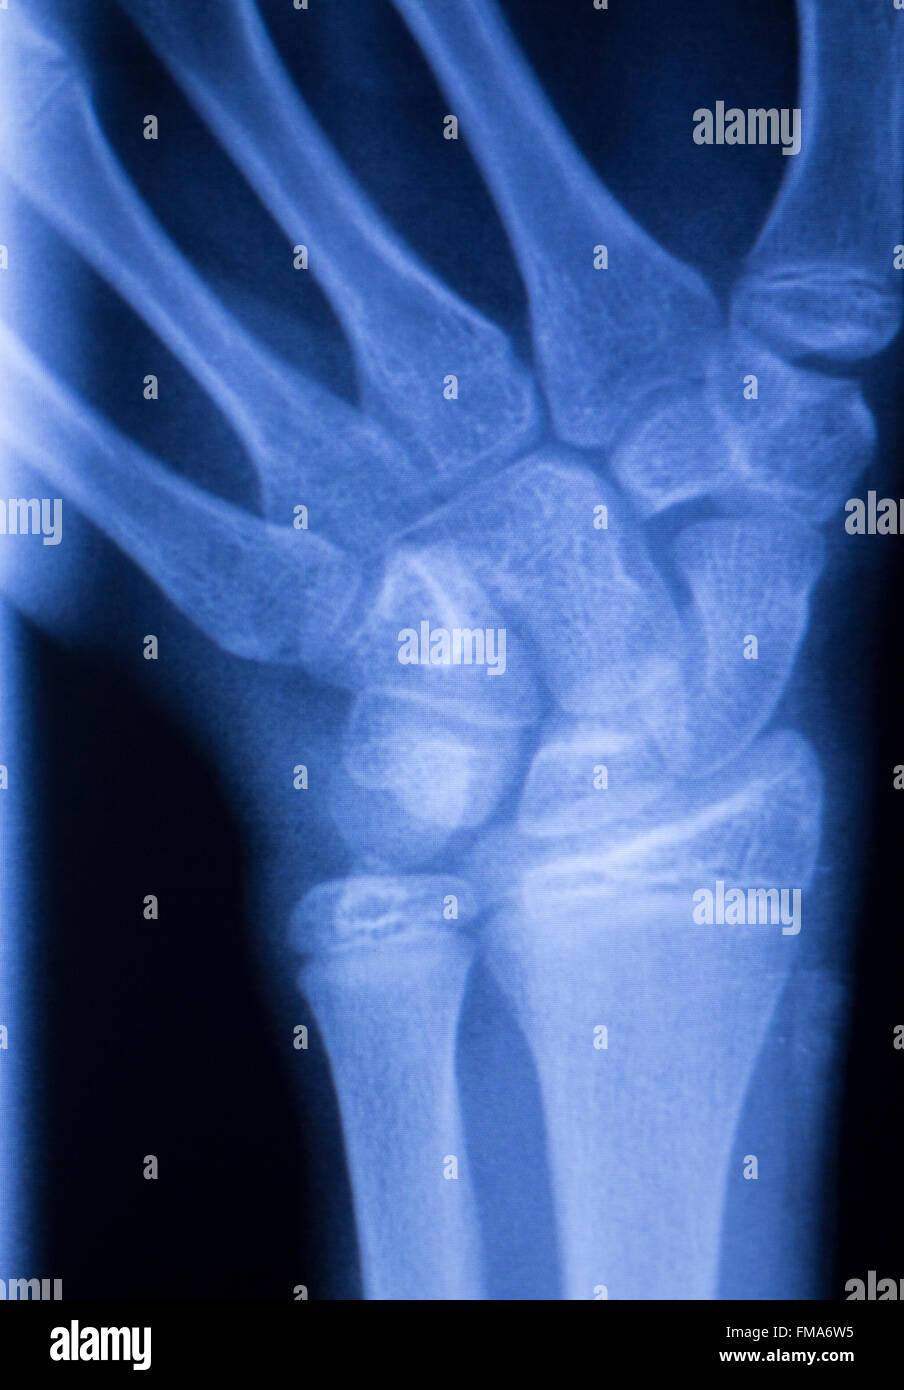

From www.alamy.com

Hand, fingers, thumb and wrist injury orthopedic Traumatology medical x Wrist Injury Evaluation this topic review will provide an overview to acute wrist pain or injury in the adult. wrist pain is traditionally classified as acute pain caused by a specific injury or as subacute/chronic pain not caused by a traumatic event (tables 1 and 2). using information from the history, key symptoms, and findings from the basic wrist examination,. Wrist Injury Evaluation.